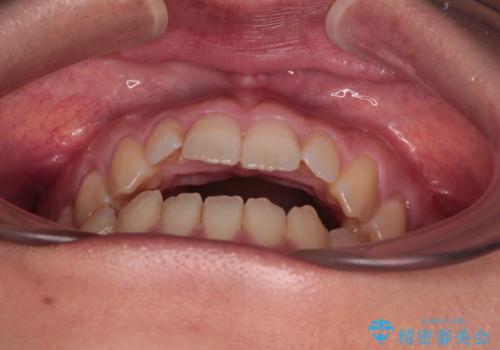

【モニター】食事が取りづらい 極端な開咬をインビザラインで解決

- 極端な開咬を気にして来院された患者様です。

開咬の方の特徴として、幼少期の指しゃぶりの癖や、強い舌の突出癖が挙げられます。

こちらの患者様も強い舌の突出癖が認められたため、矯正治療を行うにあたり、舌のトレーニングをしっかりと行っていただくように指示をいたしました。

開咬はインビザラインが得意とする歯列不正であるため、舌のトレーニングを行いながら、インビザラインにて矯正治療を行うこととしました。